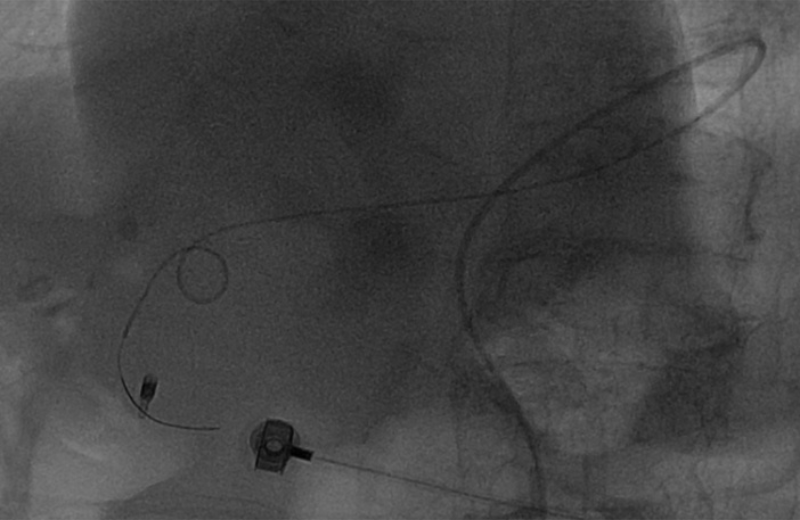

更換造影導管及反復嘗試后,導管進入腹腔干動脈。

造影顯示肝總動脈發出胃十二動脈及肝左右動脈。但胃十二指腸多處彎曲,微導管進入胃十二指腸動脈遠端困難,更換成超細導絲后最后將微導管送入胃十二指腸動脈遠端。